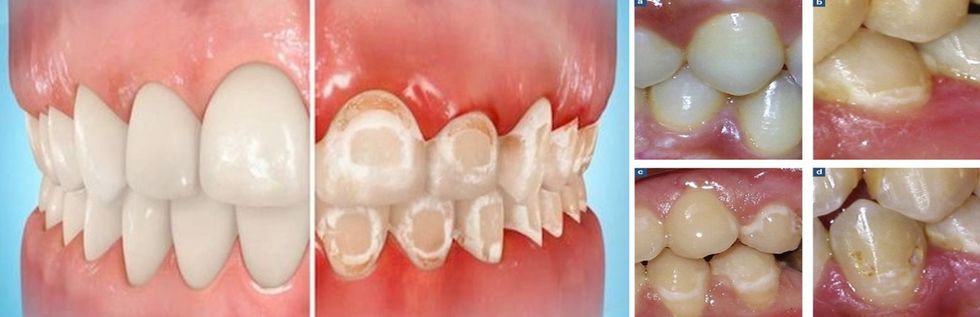

Dallimi mes strukturës së shëndoshë të dhëmbëve dhe dëmtimi i strukturës së tyre nga mungesa e vitaminës D

▪ Kariesi apo prishja e dhëmbëve ndodh brenda një afati kohor shumë të shpejtë dhe të shkurtër, ku struktura e dhëmbëve është e brishtë dhe e demineralizuar.

▪ Dhëmbët kanë strukturë të dobët, që thyhen lehtësisht apo krijohet derdhje e strukturës së tyre, e cila pastaj është teren i përshtatshëm për retencion dhe atakim nga kariesi dhe sëmundjet gingivale e parodontale (sëmundjet e mishrave dhe shtratit të dhëmbit).

▪ Dhëmbët duken të plasaritur, kjo mundëson thyerje të lehtë të tyre.